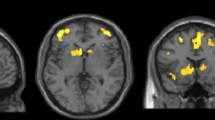

TBSS (v 1.03), part of the FRMIB Software Library (FSL), was employed as a complementary analysis tool for diffusion parameters in the thalamus. Comparisons were performed in PSP vs controls in the derivation cohort and in PSP vs controls, PD and MSA-P in the validation cohort (Fig. 2) [34]. FA and MD maps were registered onto the 1 mm3 FMRIB58 FA template in MNI152 standard space, using the linear and nonlinear registration tools FLIRT and FNIRT [35, 36]. Before registration, the diffusion maps were masked with the FSL Brain Extraction Tool (BET) [37]. The normalized maps were skeletonized by projection onto the FMRIB58 template skeleton. Finally, the skeletonized maps were masked to include only voxels from the thalamus. The masking was done using the left and right thalamus regions in the MNI152 space Harvard-Oxford subcortical atlas, together with the requirement that the MD of the normalized maps must be less than unity in the control subjects of the derivation cohort [38].

Fig. 2 Areas in thalamus with significantly decreased fractional anisotropy and increased mean diffusivity in patients with progressive supranuclear palsy when compared to healthy controls. Results of the tract-based spatial statistics (TBSS) analysis in the thalamus, showing regions of significant decreased fractional anisotropy (red voxels) and increased mean diffusivity (blue voxels) in patients with progressive supranuclear palsy when compared to healthy controls. a and b correspond to the derivation cohort, while c and d correspond to the validation cohort. Green voxels are voxels on the TBSS-skeleton where no significance was found

In the derivation cohort, PSP patients showed significantly higher MD than controls in 75 % of the skeletonized voxels in the thalamus (Fig. 2). In the validation cohort, patients with PSP were found to have a higher MD in the thalamus than controls (75 % significant voxels). In the derivation cohort, a higher MD was also found in the PSP group compared to both PD (67 % significant voxels) and MSA-P (53 % significant voxels). Furthermore, a reduced FA was observed in PSP vs controls in both cohorts and in PSP vs IPD in the derivation cohort (30–50 % significant voxels).